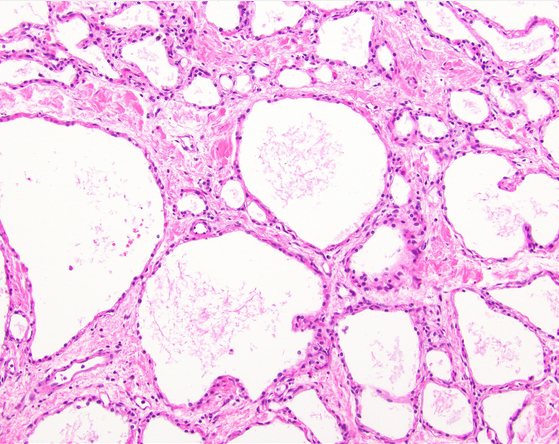

59F incidental 2.5cm mass in pancreatic body

dx

Key features

Localisation

demographic

diagnostic molecular

A

Microcystic serous adenoma

Key features: Essential: usually a cystic lesion; low, cuboidal, bland glycogenated epithelium.

Localisation: Mostly body/tail of pancreas (50-75%)

Demographic: female predominance

Diagnostic molecular: VHL is considered the main tumour suppressor gene responsible for the formation of both familial and sporadic serous cystadenomas

72F 2cm mass pancreatic tail, incidental finding

dx molecular

Serous cystadenoma

Genomic alterations in VHL